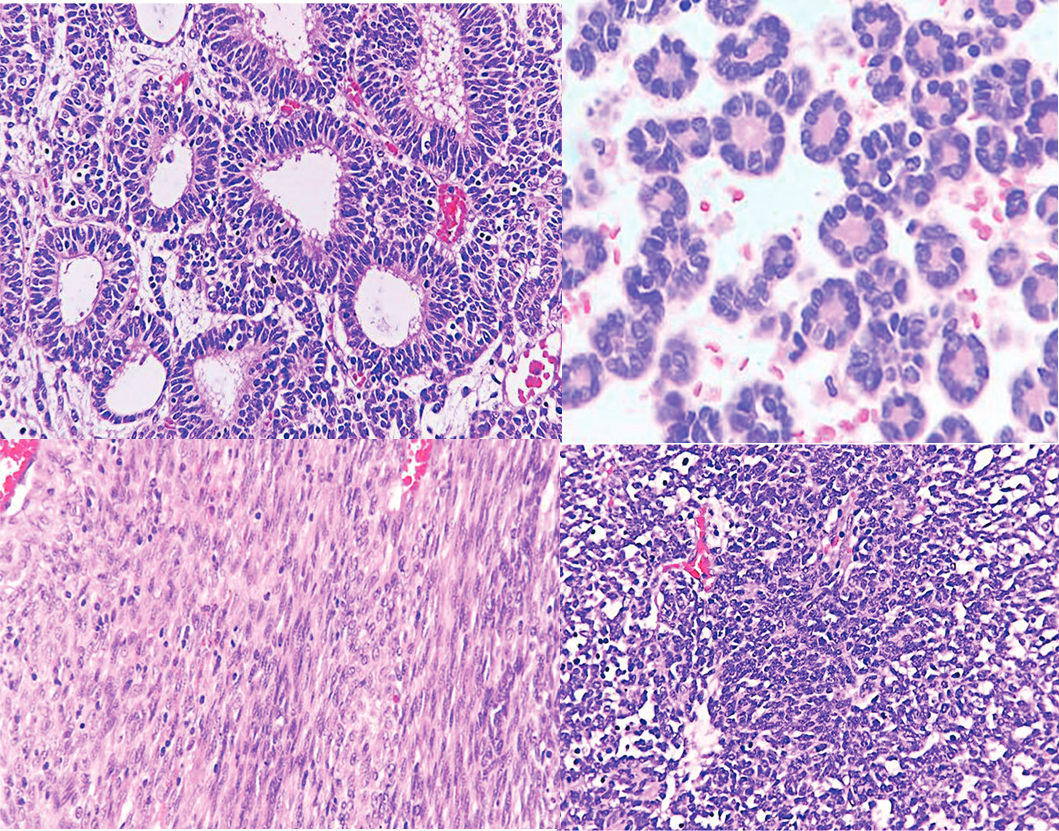

Nephroblastoma in a 51-year-old Male

An Exceedingly Rare Occurrence of Malignant Embryonal Tumor in Adulthood

Eldimson Bermudo, Jon Paolo Tan, Al-Zamzam Abubakar

25-30